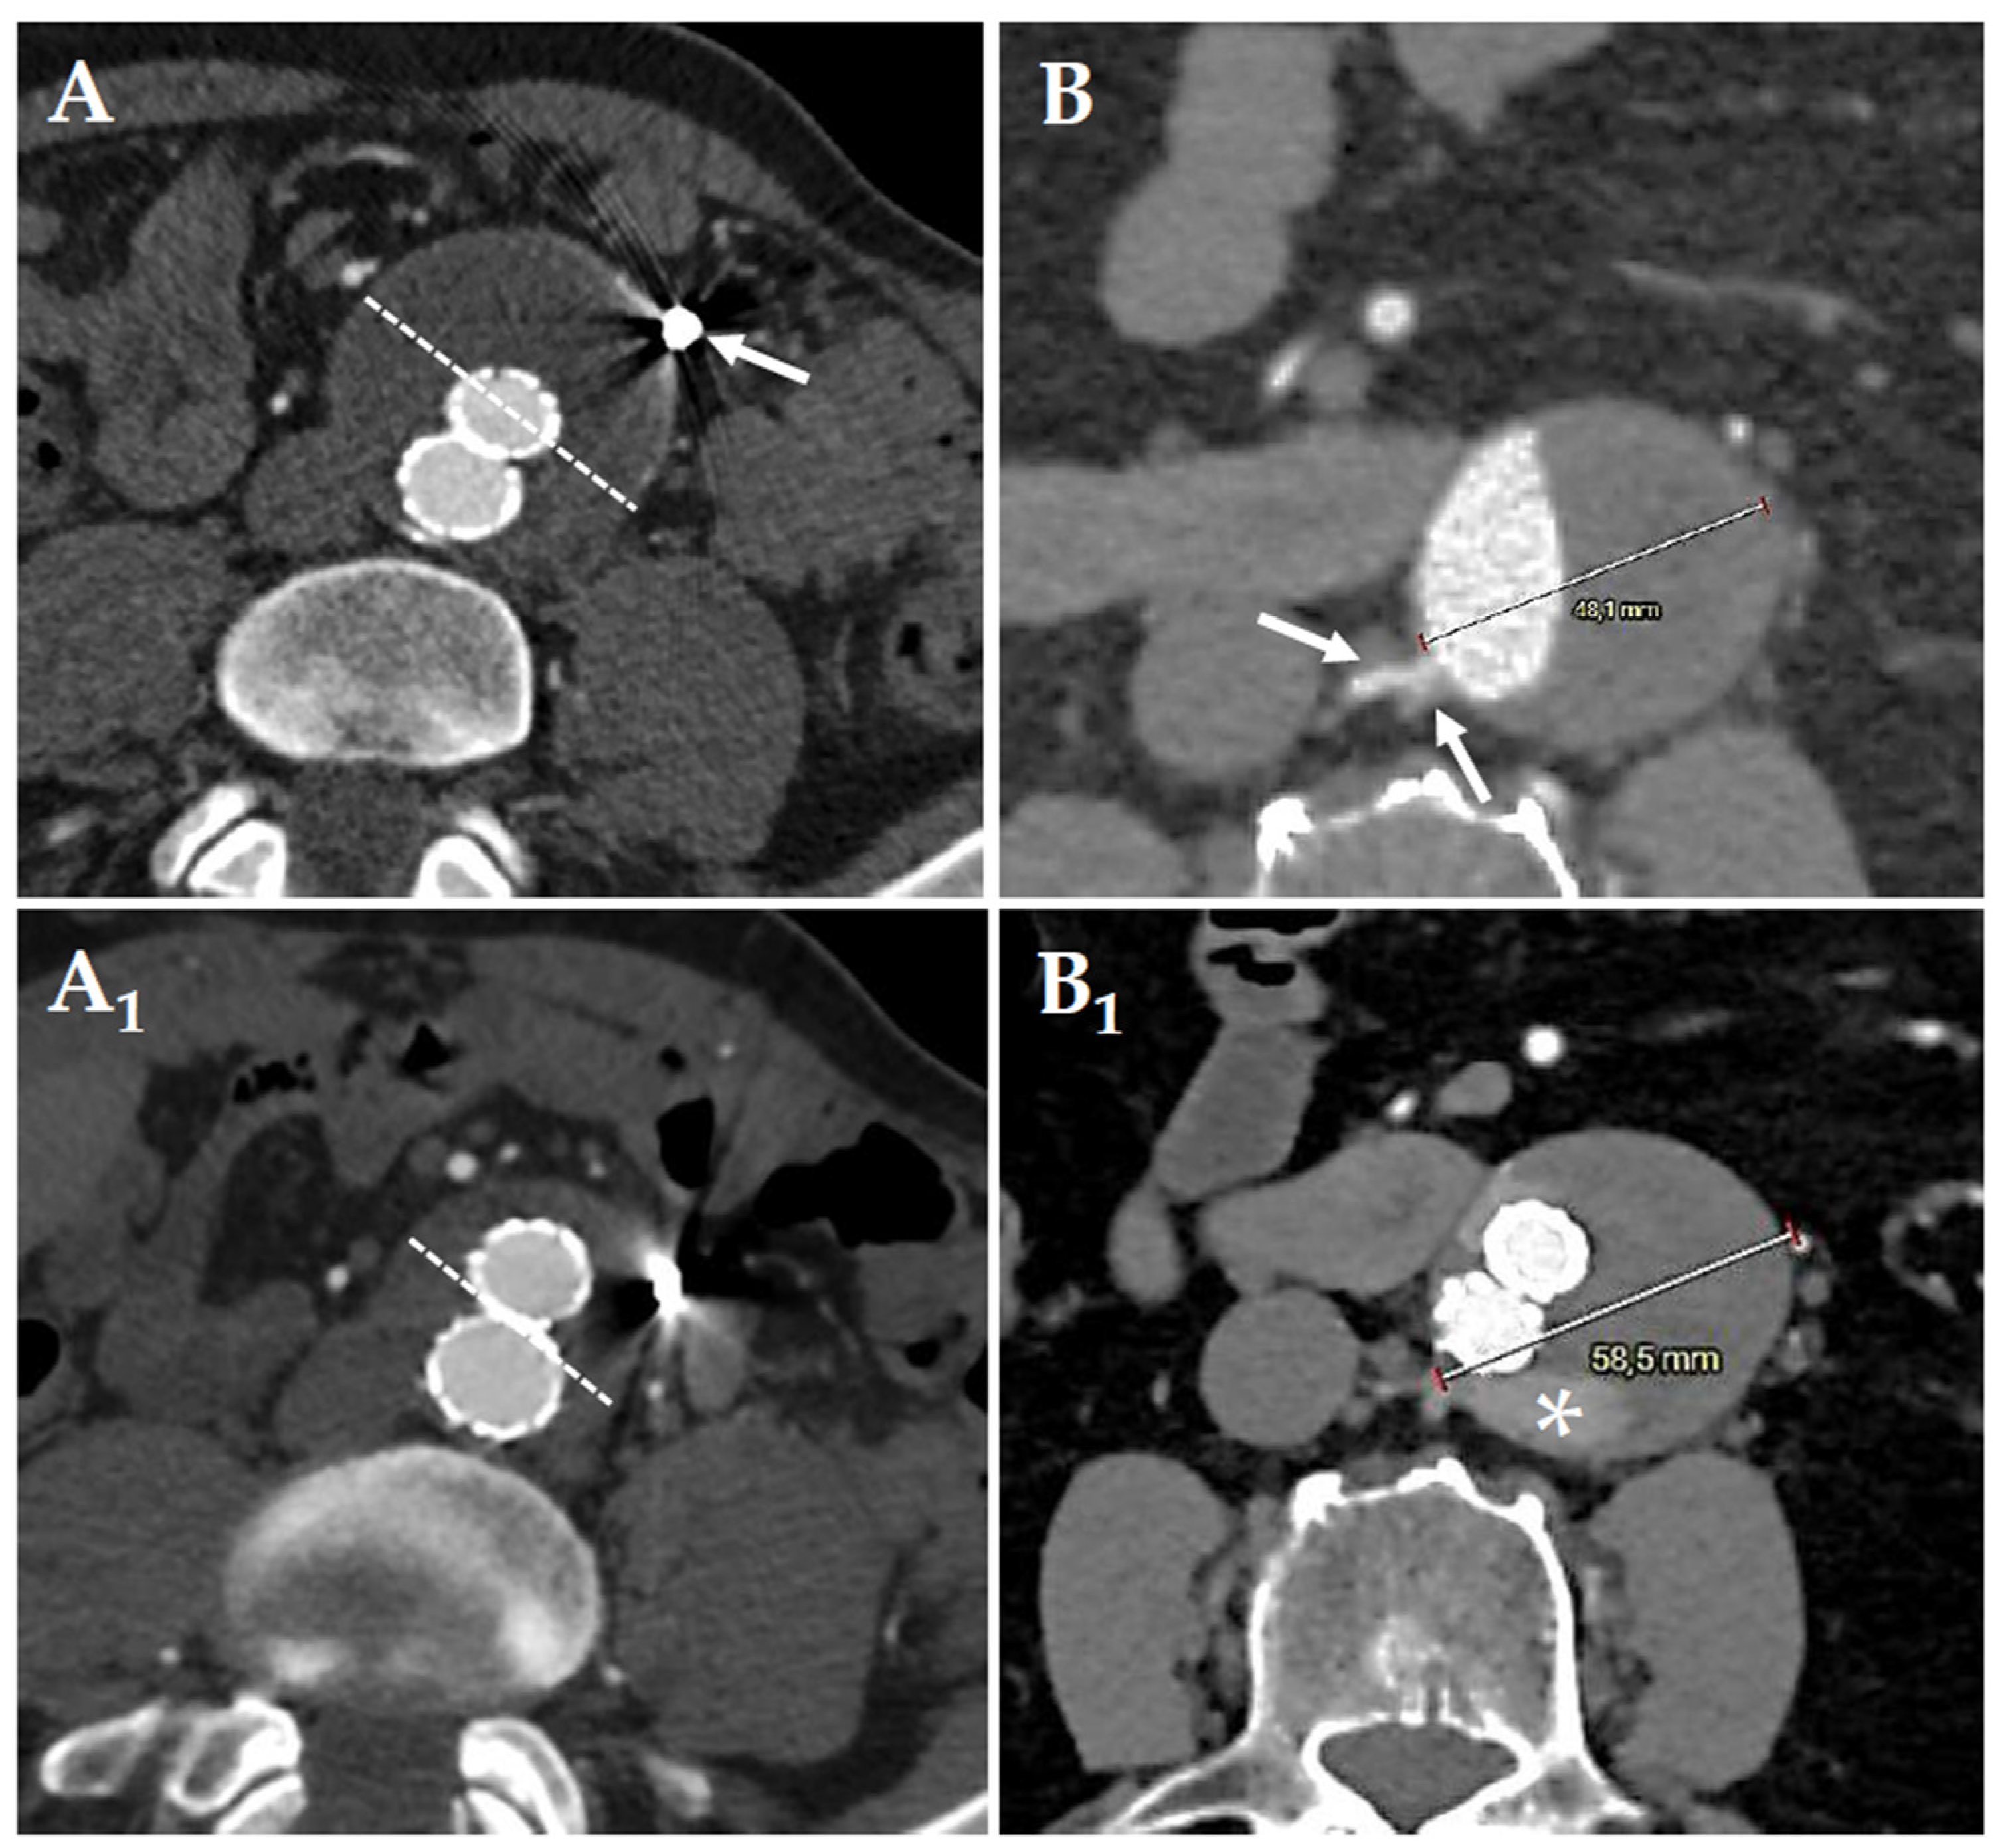

Figure 2. Preoperative (A) computed tomography-angiography of preemptive embolization of the inferior mesenteric artery (A, white arrow). Postoperative (A1) follow-up shows a shrinkage of the aneurysmatic sac (A,A1; sketched white lines). Preoperative (B) computed tomography-angiography of standard endovascular aortic repair without lumbar (white arrows) preemptive embolization. Postoperative (B1) follow-up at 2 months, shows the sac enlargement (48mm-to-58mm) due to the presence of a type 2 endoleak with the “nidus” (white asterisk) fed by the pair of lumbar arteries highlighted at the preoperative computed tomography-angiography.